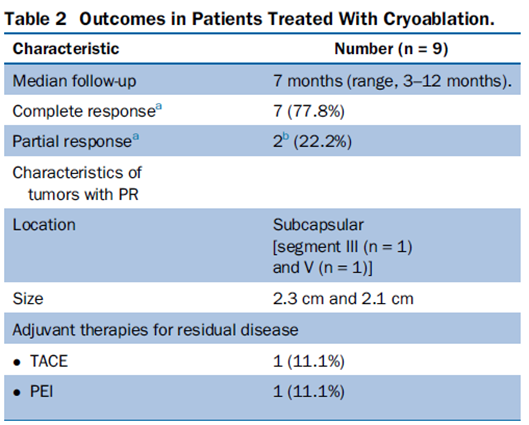

技术成功率为100%,本研究中77.8%(7/9)的患者达到了完全消融,辅助局部治疗后,所有患者均完全消融。

本研究中患者随访期间无局部肿瘤进展,无死亡病例,没有发现与手术相关的并发症。证实冷冻消融是一种有效的治疗方式,在技术上是可行和安全的。由于肝包膜下病变位置特殊,射频消融有出血及肿瘤种植的风险,可能会对邻近器官造成损伤,并且增加局部肿瘤进展的风险。近年来,冷冻消融术的应用逐渐广泛,有研究显示冷冻消融治疗具有明显优势,可治疗特殊部位的肝肿瘤。本研究的目的是评价冷冻消融治疗肝包膜下肿瘤的安全性和有效性。回顾性纳入2016年7月1日至2018年9月1日期间冷冻消融的57例患者。包括42例男性和15例女性,平均年龄为62.4岁(范围:48-82岁)。每个患者有1个或2个平均肿瘤尺寸为2.4cm的病变(范围:0.6-4.0cm)。所有患者均患有慢性肝病或肝硬化,并伴有乙型肝炎(n=52)、丙型肝炎(n=3)和其他肝炎(n=2)。根据肿瘤位置,在膈肌或肝脏下附近有18个病变(26.5%),胃或肠附近有9个病变(13.2%),腹壁附近有33个病变(48.5%),肾脏附近有8个病变(11.8%)。

完全消融率为97%(66/68);2名患者均接受了额外的冷冻消融,随后实现完全消融。平均随访期为 12.8 个月(范围:3-27 个月)。所有患者均接受影像复查(CT 或 MRI)。11个病灶(16.2%)检测到局部肿瘤进展,6、12和18个月时的累积局部肿瘤进展率分别为4%、8.2%和20.5%。8例出现远处肝内或肝外病变的患者接受经动脉化疗栓塞、经动脉化疗栓塞加射频消融治疗或全身化疗。

主要和次要并发症发生率分别为3.5%(2/57)和22.8%(13/57)。并发症主要表现为局部皮肤冻伤、中度气胸、发热,仅有少数患者接受治疗,多数患者自行恢复。所有患者能耐受围手术期疼痛,VAS 评分范围在 1-3 分之间(平均 1.65分)。3例患者术后疼痛加重,VAS评分达到4~5分,患者口服止痛药后逐渐缓解。所有患者术后1天血常规、白细胞计数均升高,血小板均有不同程度下降,但变化值均在正常范围内。肝功能1个月后逐渐恢复到正常水平。